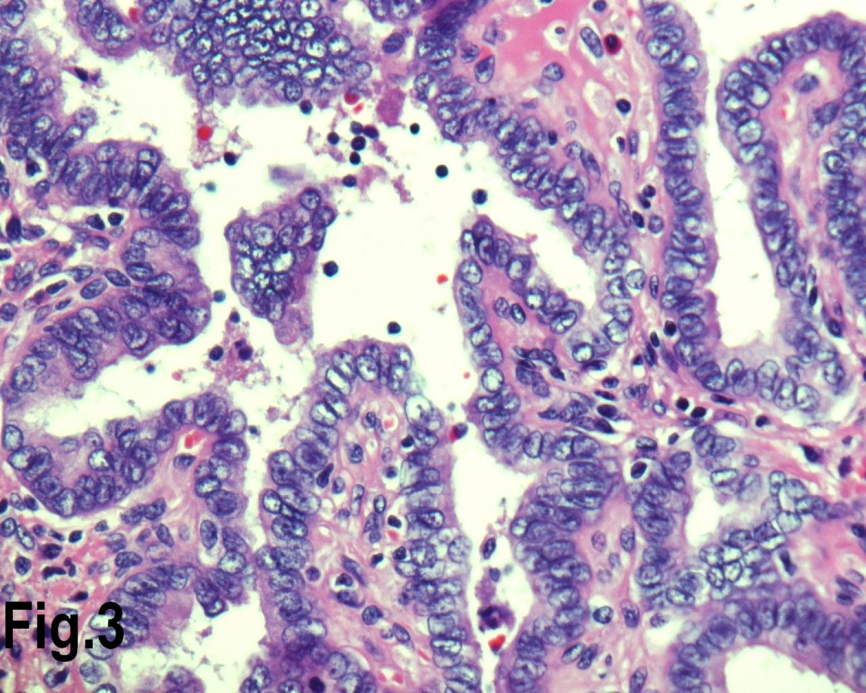

Figure 3.High power view showing follicles lined by cells with nuclear characteristics of papillary carcinoma, with prominent intra nuclear inclusions (Hematoxylin & eosin, original magnification ×400).

Solitary benign adenomas were found in 23 cases, the peak frequency was fourth and fifth decade. Female accounted for 12 cases (70.5%) for follicular adenoma (Figure 2) and 3 cases (50%) for Hurthle cell adenoma. Thyroid malignancy and it was reported in 62 cases. Papillary carcinoma (Figure 3) was the most common type of thyroid malignancy found in 44 cases (71%) followed by follicular carcinoma (9.6%) (Figure 4), medullary carcinoma (1.6) and poorly differentiated carcinoma (1.6%) (Table 3). The peak incidence for patients with thyroid malignancy in this series was third decade and male to female ratio was 3.7:1.